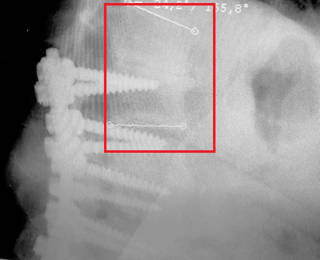

Para conseguir una buena soldadura se requiere que no haya movimiento, la ausencia de movimiento permite el crecimiento óseo lo cual se consigue mediante el uso de los famosos tornillos, barras y dispositivos intersomáticos (son cajas que se ponen entre las vértebras para aumentar la estabilidad y favorecer la fusión).

Fusiones vertebrales 360º (PLIF Y TLIF): Se denominan fusiones 360º porque además de intentar que se fusionen las articulaciones facetarias también intentamos que se fusionen los cuerpos vertebrales. Para ello tenemos que quitar el disco lumbar e introducir una caja entre los cuerpos vertebrales que rellenamos de injerto. La ventaja de las fusiones 360º es que aumentamos el porcentaje de éxito de la cirugía ya que la caja intersomática aumenta el área de fusión y da más estabilidad al montaje.